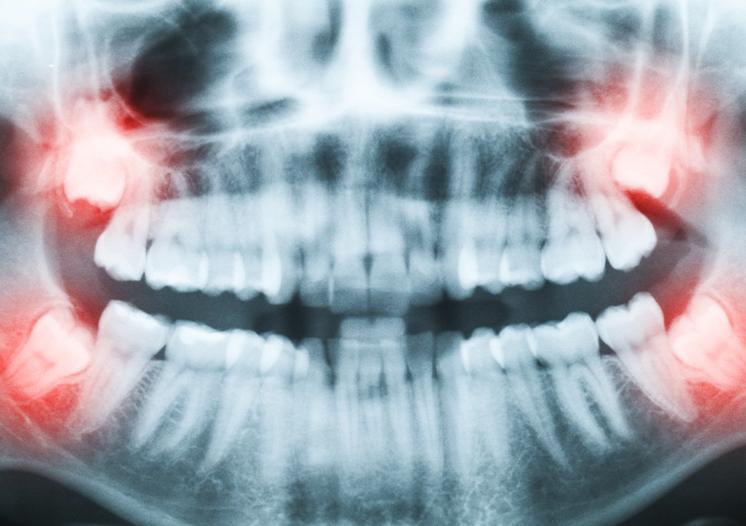

Your wisdom teeth are typically the last teeth to develop. There is sometimes not enough room to accommodate the wisdom teeth which impedes their ability to erupt into the mouth correctly. In some cases, the wisdom teeth will partially emerge through the gums and can result in cavities, crowding, or gum infections. Wisdom teeth will often develop diagonally and horizontally, causing significant problems. This uneven development may be responsible for a myriad of oral health problems which include teeth crowding and damage to the adjacent second molars.

When there is not enough space for the wisdom teeth to erupt at all, they can cause pain in the gums and bone as they shift. This is known as ‘Impacted Wisdom Teeth.’ When your wisdom teeth are impacted, the opening around the teeth may become a fertile ground for bacteria to start developing and may lead to an infection in the gum tissues. As a result of this infection, you may experience discomfort, swelling, pain, and illness. The early removal of impacted wisdom teeth is often recommended to avoid future problems and to avoid costly surgical procedures.

Dr. Struan Vaughan and Dr. Matt Cosman will complete a thorough examination of your mouth, including x-rays that will help diagnose the type of wisdom teeth removal you require. Regular dental exams also help you keep your gums and teeth healthy, allowing us to identify any potential concerns to prevent costly dental procedures down the road.

If your wisdom teeth are aligned properly, and the surrounding gum tissue is healthy, wisdom teeth do not always have to be removed. With our clinical exam and panoramic imaging, we can inform you if you or your child’s wisdom teeth require extraction.